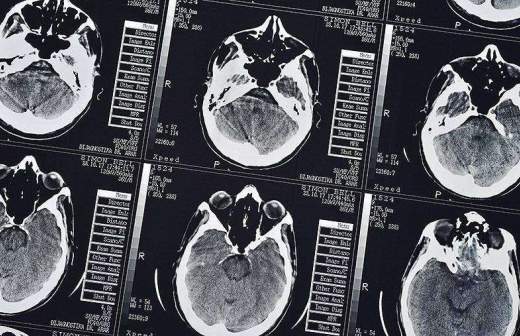

Найден способ замедлить старение мозга

Фото: TASS/DPA/Ralf Hirschberger

Кетогенная диета способна улучшить когнитивные способности и снизить риск развития нейродегенеративных заболеваний. К таким выводам пришли ученые из Кентуккийского университета (США), проведя опыты на мышах.

Кетогенная диета отличается малым содержанием углеводов и высоким — жиров. Ученые утверждают, что такой рацион положительно влияет на кровоснабжение мозга и гематоэнцефалический барьер, защищающий нервную систему от токсинов и вредных микроорганизмов в крови.

Через 16 недель у первой группы грызунов улучшился баланс микрофлоры кишечника, увеличился мозговой кровоток, снизился уровень сахара в крови, а также активировался процесс очищения нервных тканей от бета-амилоидов, которые, предположительно, влияют на развитие болезни Альцгеймера.